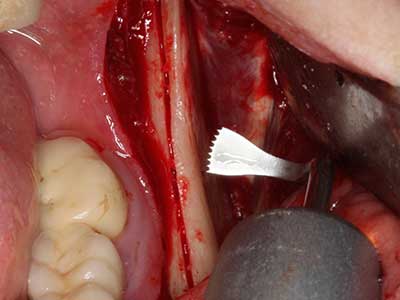

Indication: Preparation near nerves

When surgical procedures are performed on bone in the immediate vicinity of sensitive structures such as blood vessels or nerves, rotary instruments pose a significant risk of iatrogenic injury. Piezoelectric devices can be helpful for preparation of bone covers and removal of hard tissue close to nerves, particularly for exposure of nerves after iatrogenic injury but also during nerve lateralization for resective and reconstructive procedures or implant placement (Fig. 17-20). Light contact between the piezotip and the nerve does not generally result in damage but proceeding incautiously with saw-like motions or attachments where a residual bone substrate remains may cause temporary or even permanent nerve damage. However, the risk of damage is considered to be substantially lower than when using saws or milling instruments (Pereira, Gealh et al. 2014).